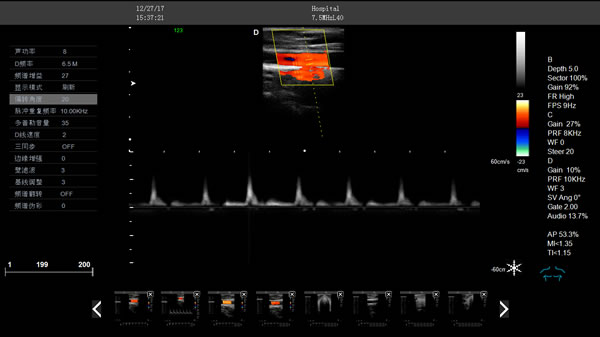

DW-CT580 全數(shù)字彩色多普勒超聲診斷儀

DW-CT580,全數(shù)字彩色多普勒超聲診斷儀,推車式彩超